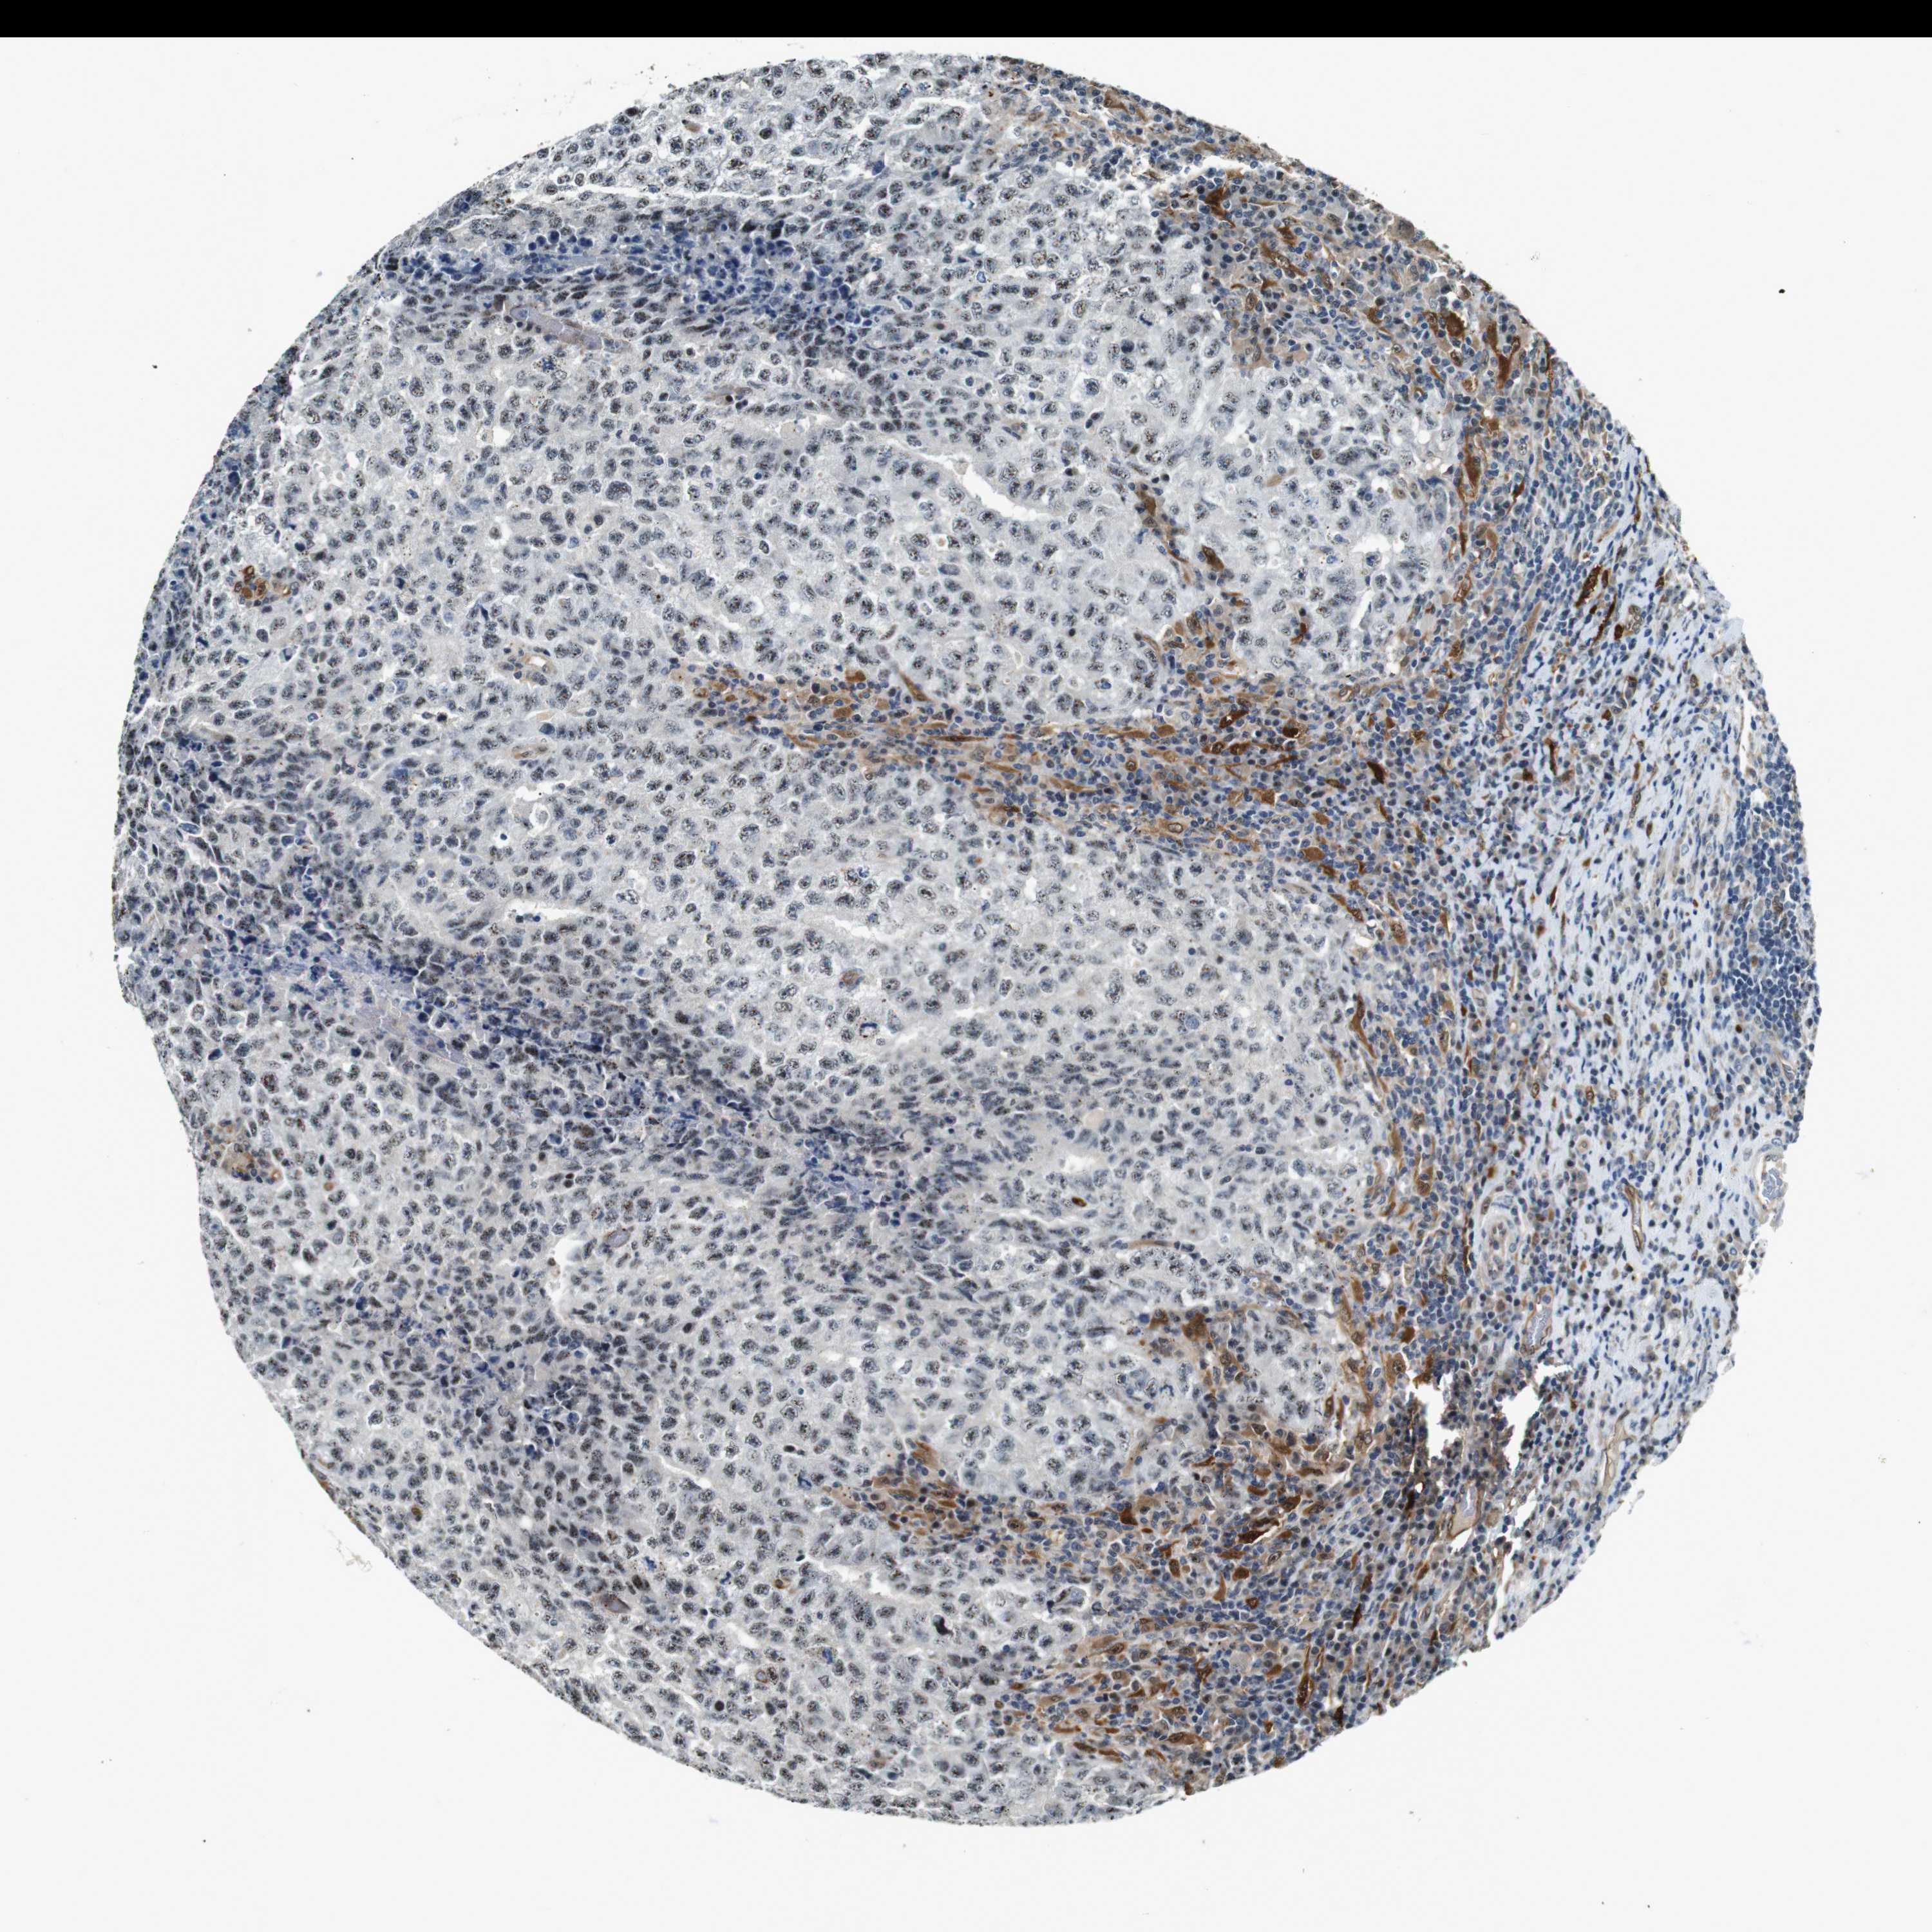

TESTIS CANCER - Protein expressioni

A mouse-over function shows sample information and annotation data. Click on an image to view it in a full screen mode. Samples can be filtered based on level of antibody staining by selecting one or several of the following categories: high, medium, low and not detected. The assay and annotation is described here.

Note that samples used for immunohistochemistry by the Human Protein Atlas do not correspond to samples in the TCGA dataset.

Antibody stainingi

Antibody staining in the annotated cell types in the current human tissue is reported as not detected, low, medium, or high, based on conventional immunohistochemistry profiling in selected tissues. This score is based on the combination of the staining intensity and fraction of stained cells.

Each image is clickable and will lead to virtual microscopy that enables deeper exploration of all samples and also displays staining intensity scores, fraction scores and subcellular localization as well as patient and tissue information for each sample.

Antibody HPA014179

Antibody CAB025128

Carcinoma, Embryonal, NOS

Seminoma, NOS